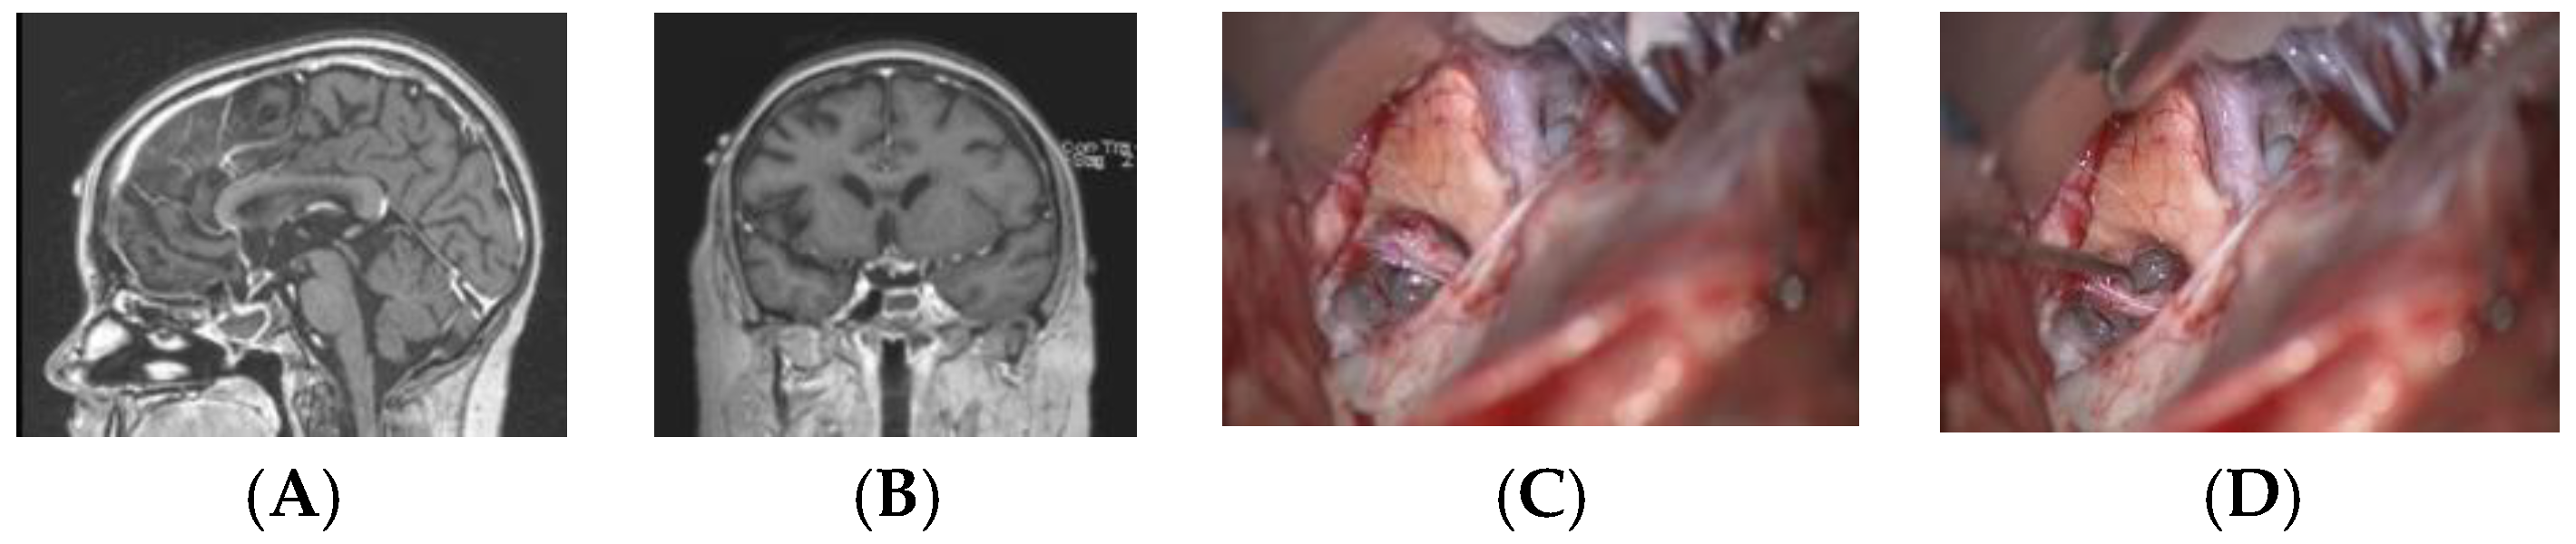

Except for the four patients who underwent primary surgical resection, MR imaging following adjuvant therapy demonstrated lesion resolution in all patients with a preserved PS and either a normal or atrophic PG (Figure 7). The PS further demonstrated anatomic continuity during second-look surgery (Figure 8).

Figure 8. Twelve-year-old girl with suprasellar tumor with β-HCG. Following chemotherapy, the β-HCG was normalized, but there was a small contrast-enhancing lesion in the left suprasellar location on MR (sagittal (A) and coronal (B) views). Surgical photographs at second-look surgery demonstrate the chiasm and an atrophic but continuous pituitary stalk (C), which is retracted by a hook (D). The lesion demonstrated no viable cells.